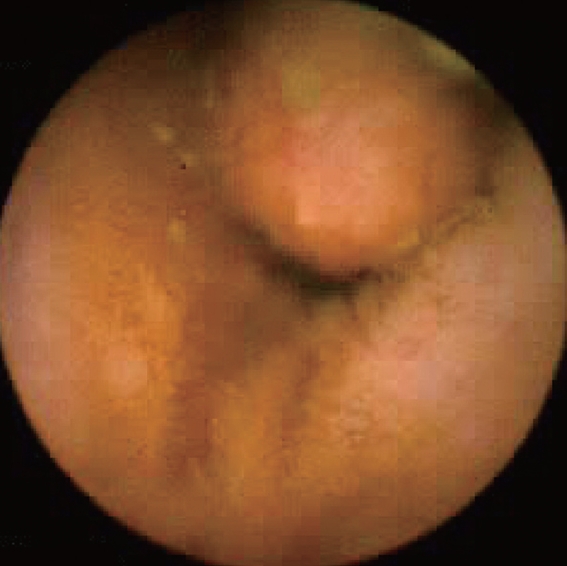

The adenocarcinoma is clearly seen nearby the ileal pouch anal anastomosis (Courtesy Dr. V. Penopoulos)

Endoscopic view of ileal pouch - anal anastomosis 3 years before the development of adenocarcinoma (Courtesy Dr. V. Penopoulos)